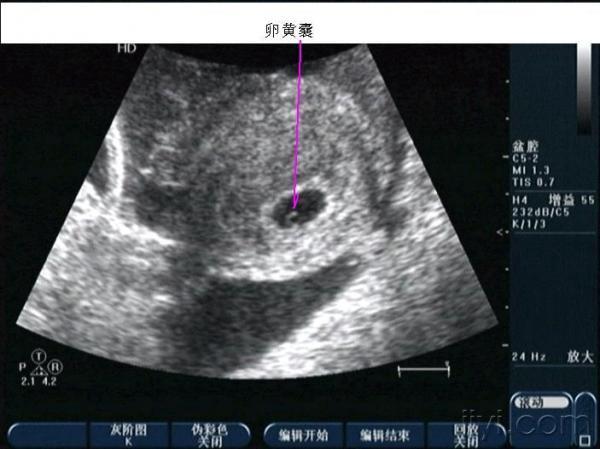

早孕并黄体破裂

晚上房事后腹痛入院,第二天早晨8点多超声所见如下,手术证术为黄体破裂。